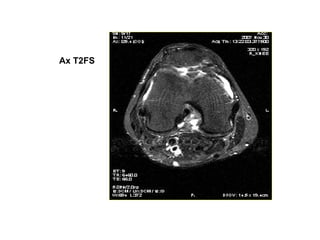

Ax T2FS

PROTOCOL CHUÏP KHÔÙP GOÁI

• Axial TIRM, PdFS

• Sagittal T2W, PdFS

• Coronal T2FS, Med3d

• Ñoä daøy laùt caét # 4mm (tröø med3d 1.5mm-20%)

• Dist. Factor # 10%